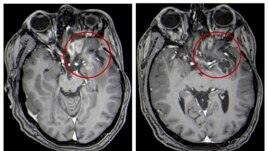

This combination of MRI images provided by the University of Alabama in April 2021 shows scans of a child with a brain tumor, before and after the treatment.

This combination of MRI images provided by the University of Alabama in April 2021 shows scans of a child with a brain tumor, before and after the treatment.